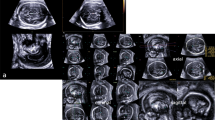

Cerebral MRI data were collected from 21 children with a complex congenital heart disease (CHD) before Fontan procedure, at a median age of 27 months (range 20.9–42.4 months). Data were segmented with SPM, FSL, and FreeSurfer, and total intracranial volume (ICV) and total brain volume (TBV) were compared with corresponding measures obtained using the Cavalieri method.

FreeSurfer provides an accurate method for measuring brain volumes in young children, even in the presence of structural brain abnormalities.